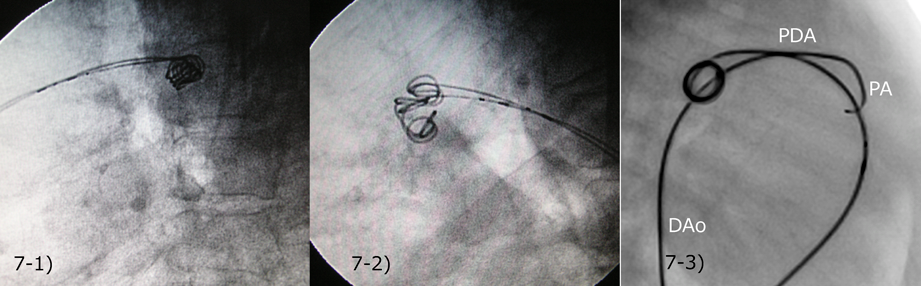

同時に複数のカテーテルをPDAに通し,複数のコイルを絡めた上で離脱する方法で,最小径4 mm前後以上のPDAで行うことが多かった.例えば2本のF-coilを同時留置する場合,肺動脈側から2本,大動脈側から2本のカテーテルを挿入して閉鎖することも考えられる(Fig. 7).しかし,2本のコイルの位置調整がやりやすい,コイルがずれにくいという理由で,われわれはほとんどの場合に両側(大動脈・肺動脈側1本ずつ)からのアプローチを採用している.最初のコイル2本を留置した後は,順次大動脈側からF-coilまたはGianturco coilなどのpushable coilを追加していけばよい.コイル追加のためのガイドワイヤーやカテーテルで,既に留置したコイルを押し出さないように注意する.

Fig. 7 Simultaneous deployment of the two Flipper® coils (F-coil)

7-1) Both F-coils were deployed from pulmonary side. 7-2) Both F-coils were deployed from aortic side. 7-3) Two delivery catheters were sitting across the PDA with one catheter from the pulmonary side and another from the aortic side. We usually deploy the larger coil first from the pulmonary side (4 coil loops in the PDA) and the smaller coil from the aortic side. When the two coils were confirmed sitting well, both coils can be detached. DAo, descending aorta; PA, pulmonary artery; PDA, patent ductus arteriosus